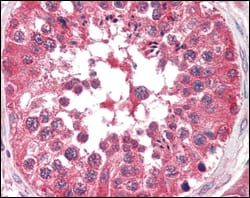

Immunohistochemical analysis of paraffin-embedded human testis tissues using BRAF mouse mAb.